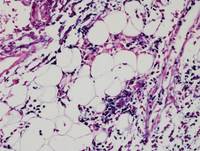

Figure 2: H&E in Hydroa Vacciniforme-like Lymphoproliferative Disorder

Features seen in the images below:

1. Epidermal degeneration with spongiotic vesiculation

2. Lymphoid infiltration in dermis and subcutaneous tissue

3. Periadnexal and perivascular infiltration by small-to-medium sized neoplastic cells without significant atypia